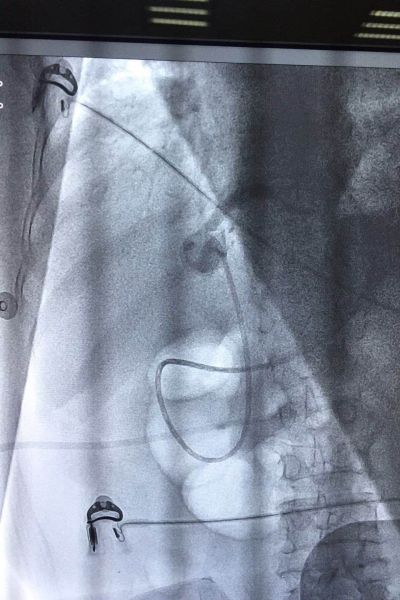

患者是一位80 岁的老年女性,因“腹痛、发热、黄疸2天”来我院求治,入院时体温39℃,血压80/40mmHg,胆红素282mmol/L,腹部CT提示胆总管下段结石,诊断胆总管结石并急性化脓性胆管炎明确。按照传统治疗方案,患者需要行外科手术。但此时手术风险极高,且术后患者需较长时间保留T管引流。有鉴于此,科主任李学锋、李凯组织消化科田家晖副主任医师、向仍运主治医师以及肝胆外科专家进行会诊,最终决定,予以患者施行急诊鼻胆管引流术。经过有序的术前准备,在外科的通力配合下,在李学锋主任和李凯主任的指导下,向仍运主治医师通过十二指肠镜对胆总管进行插管,插管成功后首先抽吸出脓液减压,再对胆总管进行造影显示出结石的位置、形态及大小,最后在结石以上胆管置入鼻胆管引流。手术过程非常顺利,历时不到40分钟,术后患者疼痛即消失,血压、白细胞、胆红素很快恢复至正常。

ERCP即逆行胰胆管造影,用十二指肠镜在X线透视下对胆管、胰管进行显影,并对病变进行相应治疗,属于四级手术。特别适用于胆总管结石、急性化脓性胆管炎、梗阻性黄疸患者。该操作无需麻醉,痛苦小(相当于做胃镜)。